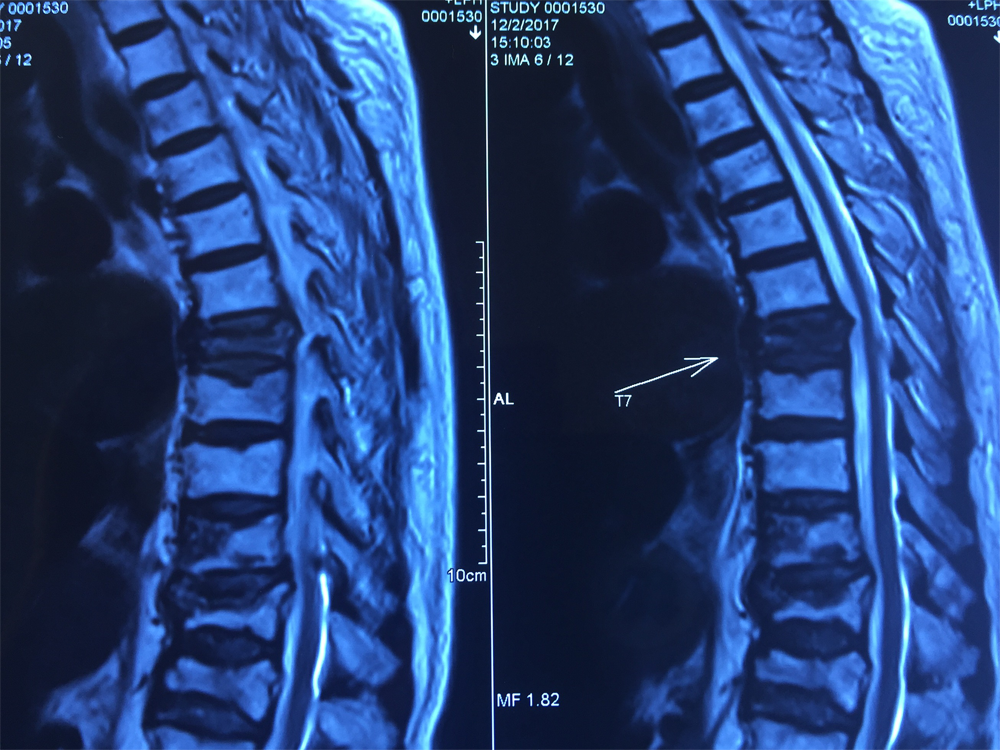

87岁的患者刘女士因腰背部疼痛剧烈,翻身活动困难而入院。入院前,刘女士及其家人四处求医问药,于外院诊断为陈旧性的腰椎椎体压缩骨折,由于患者年龄较大、手术风险较高,嘱其卧床休息,未给予特殊处理。入院后,刘维克主任对患者进行了详尽的检查,发现病位是胸椎7、10节段的新发椎体压缩骨折,如不进行手术干预,患者将遭受更长时间的痛苦。我院脊柱外科考虑该患者已87岁高龄,既往患有高血压、支气管炎、肺栓塞、心房颤动等基础疾病较多,刘维克主任及其团队经过反复论证,为患者设计了微创而高效的手术方案。

术 前